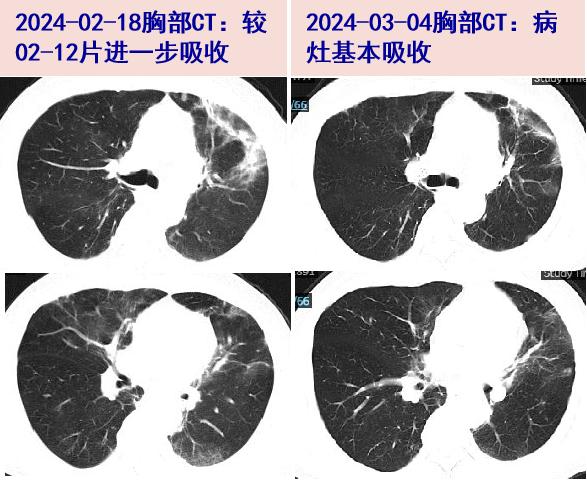

放射性肺炎-ppt

radiation pneumonitis